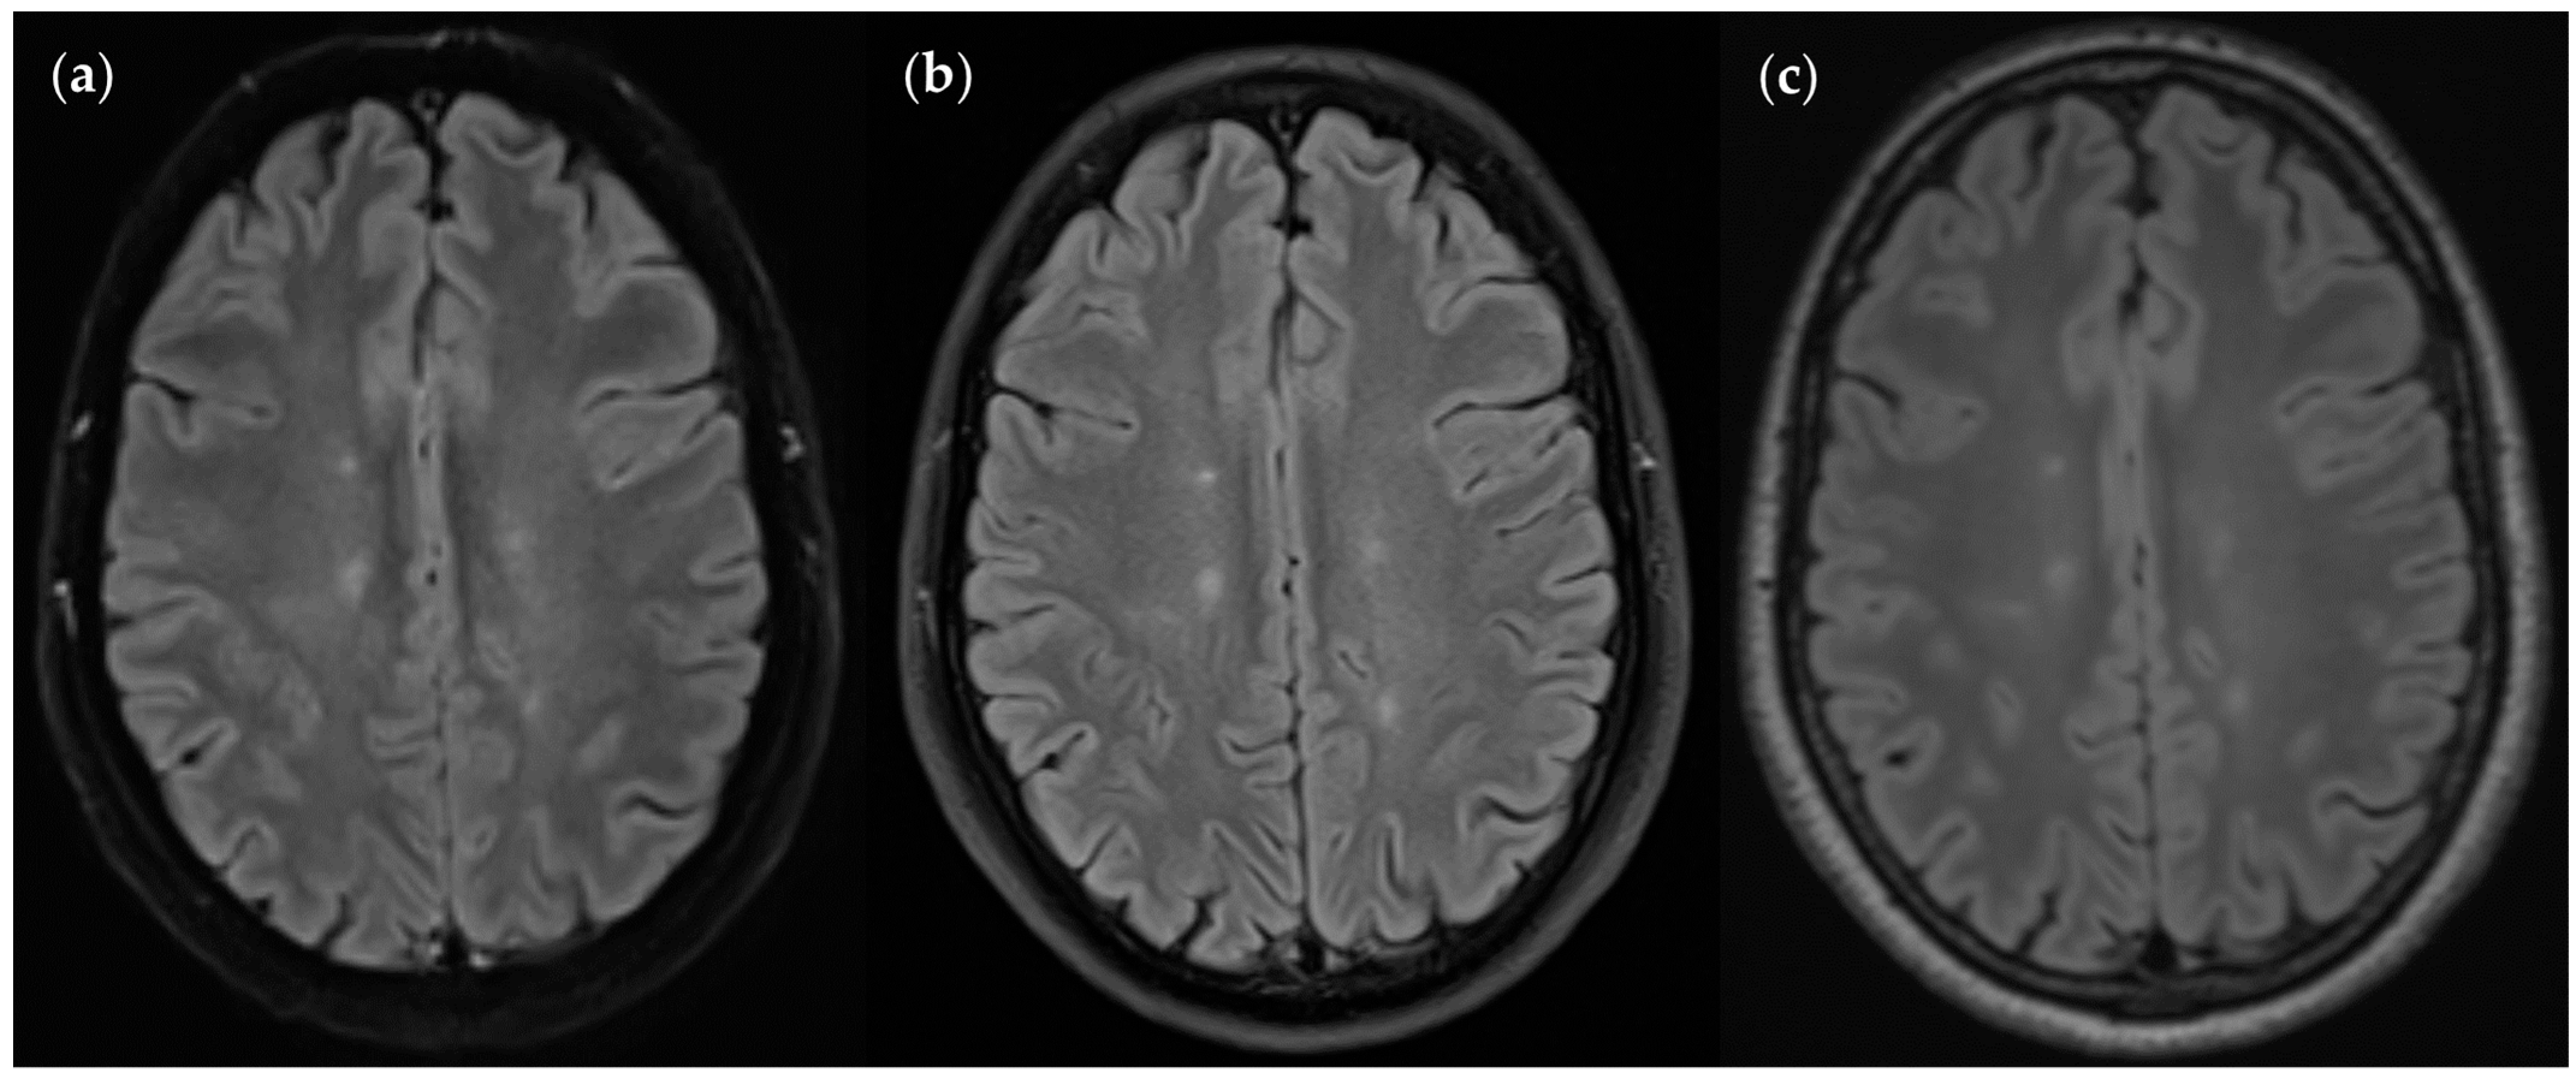

3.2.1. FLAIRUF Compared with FLAIR3Da

3.2.3. Dependence on Size and Location within FLAIRUF

3.3. Image Quality

3.3.1. FLAIRUF Compared with FLAIR3Da

3.3.3. Positional Dependence of SNR and CNR in FLAIRUF

4.3. Limitations of the FLAIRUF Images

4.4. Considerations on Ratings for Lesion Conspicuity in FLAIRUF

4.5. Outcomes Correlated with Technical Features